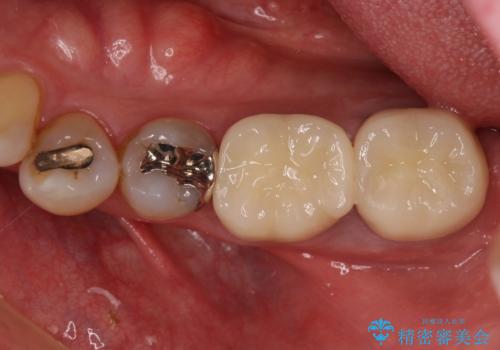

部分矯正を併用した奥歯のインプラント補綴治療

- 奥歯を他院で抜歯した後、インプラント治療を希望とのことで来院された患者様です。

ブリッジの支台を抜歯したことで2本のインプラントが必要であり、その後方はインプラント埋入に必要な骨量が不足していたため、上顎洞粘膜の挙上を行うこととしました。

また、残っている最後方歯は手前に倒れてきていたため、部分矯正により奥に移動させてから、インプラント埋入を行うこととしました。